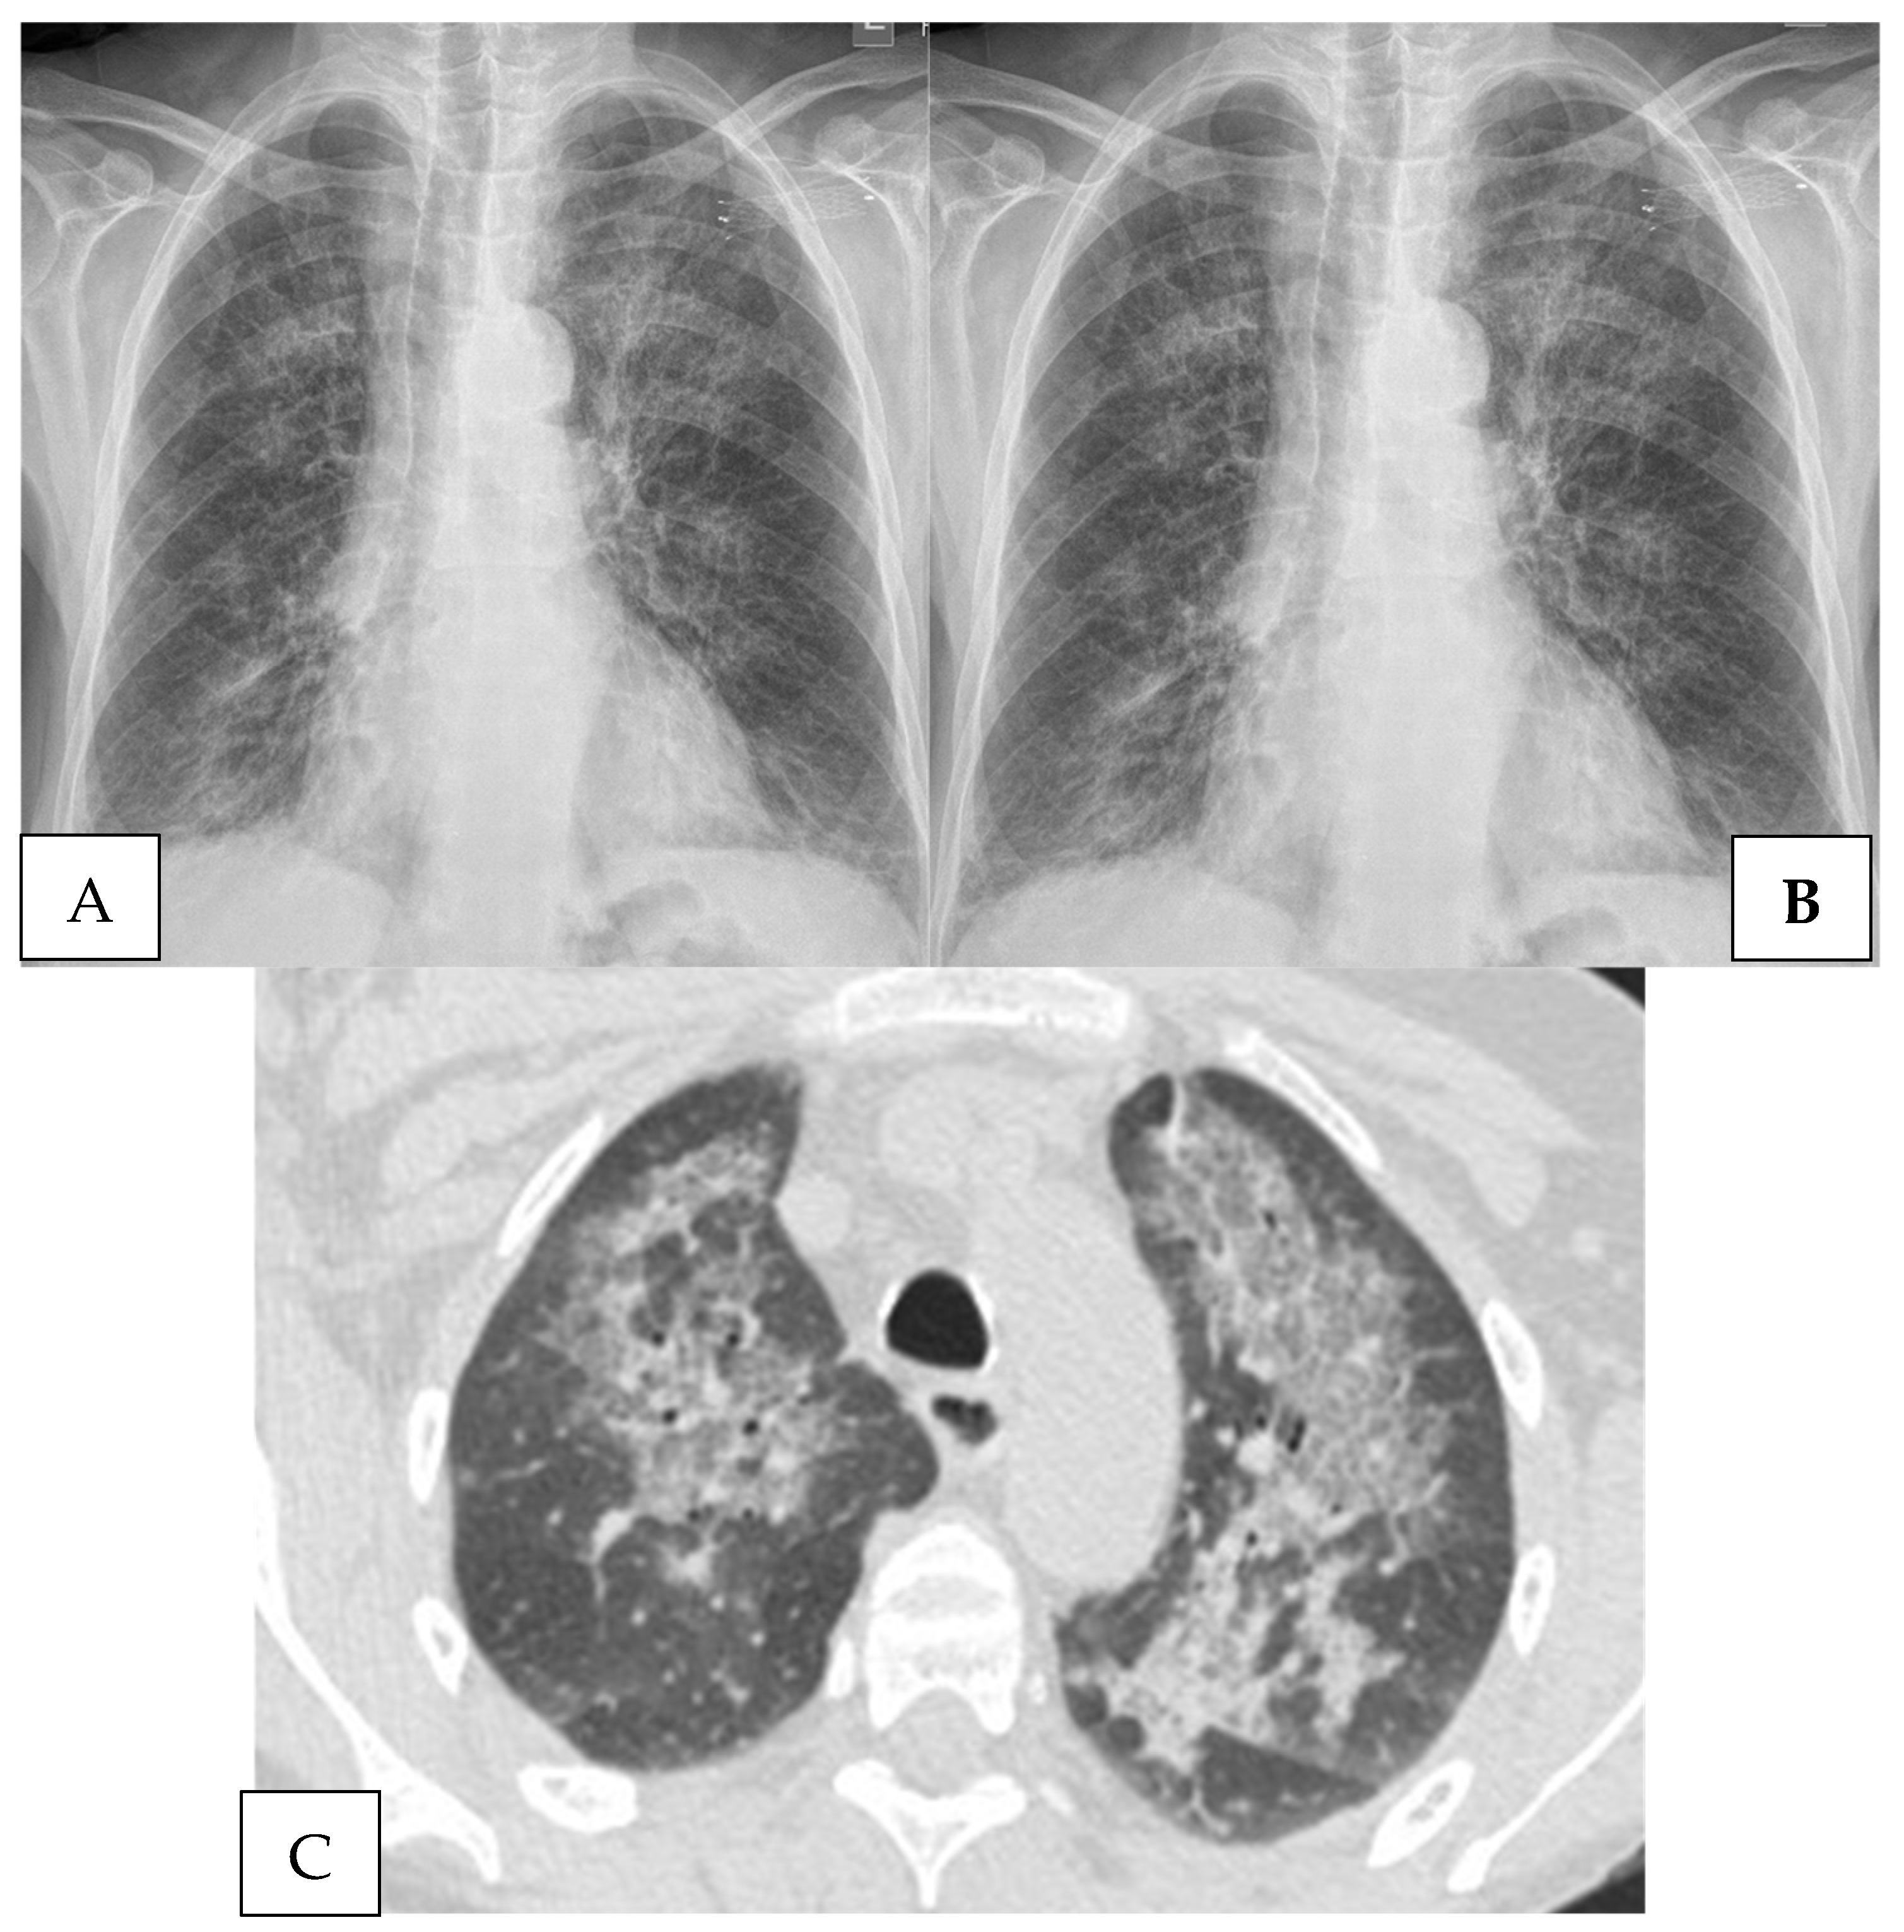

4.2. Radiography